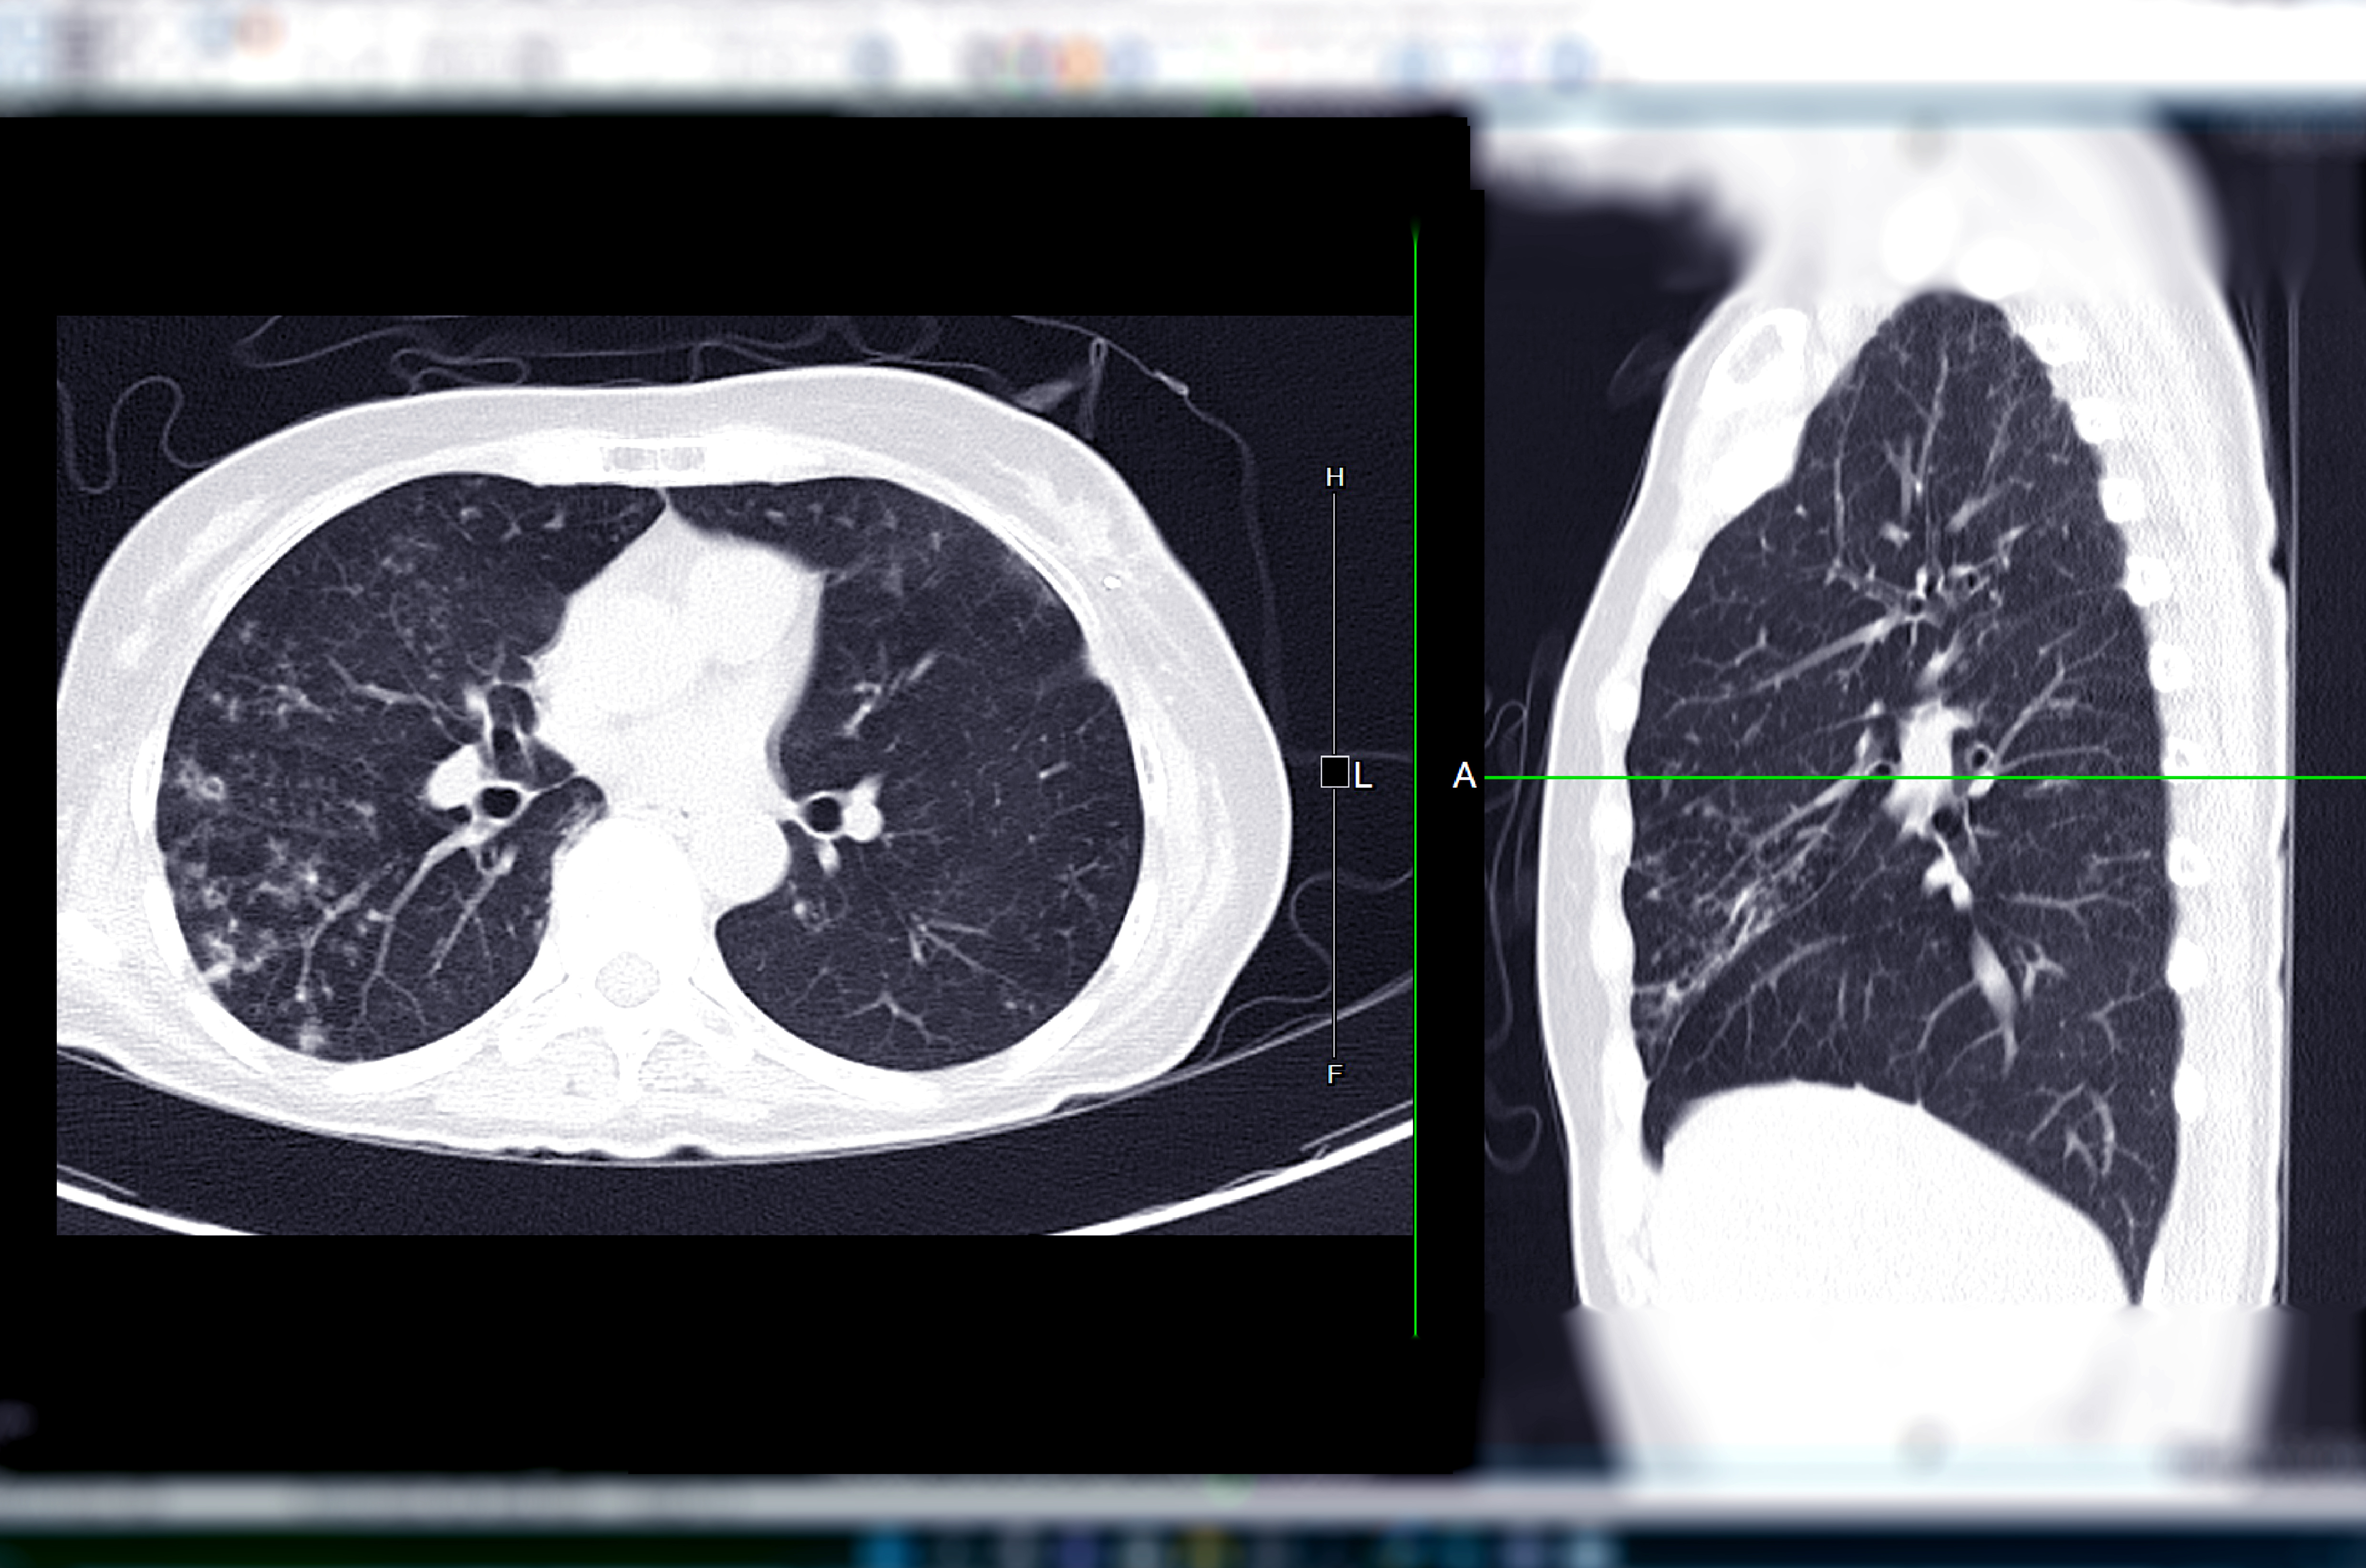

While recent recommendations from the United States Preventive Services Task Force (USPSTF) to lower lung cancer screening thresholds significantly expanded eligibility for screening tests such as low-dose computed tomography (CT), differences in education, health-care insurance and proximity to health-care facilities continue to be key drivers of racial and socioeconomic disparities limiting access to appropriate preventive care.

Emerging research shows a 14.5 percent increase among African Americans getting screened for lung cancer, which may be attributable to the United States Preventive Services Taskforce (USPSTF) lowering the minimum screening age to 50 and decreasing the smoking intensity screening threshold from 30 pack years to 20 pack years in March 2021.